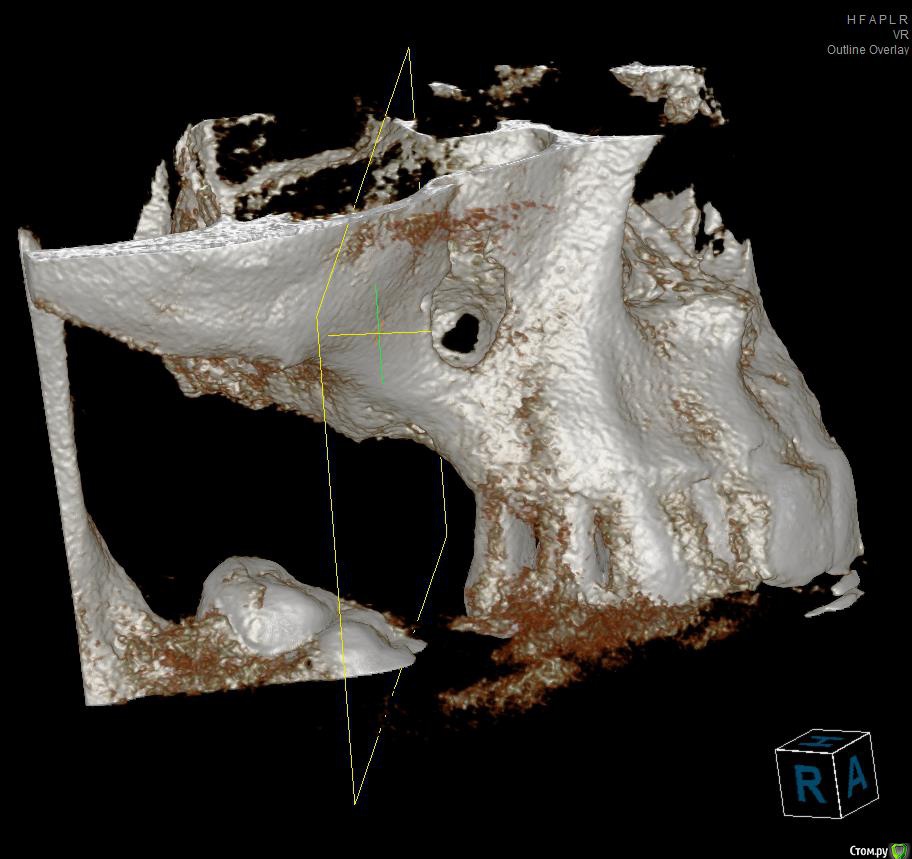

Jurai Опубликовано 19 мая, 2016 Поделиться Опубликовано 19 мая, 2016 Вот такой пациент: Больше года назад выполнена радикальная гайморотомия, с созданием соустья по поводу изменений слизистой в синусе. Сейчас картина такая. Ортопед желает два имплантата, а я что-то в сомнениях - платформы на уровне апексов меня не привлекают. Прошу вашего мнения, что возможно здесь сделать? По поводу непрозрачности синуса - ЛОР дает добро. Ссылка на комментарий

ILGAMSA Опубликовано 19 мая, 2016 Поделиться Опубликовано 19 мая, 2016 Вот такой пациент: Больше года назад выполнена радикальная гайморотомия, с созданием соустья по поводу изменений слизистой в синусе. Сейчас картина такая. Ортопед желает два имплантата, а я что-то в сомнениях - платформы на уровне апексов меня не привлекают. Прошу вашего мнения, что возможно здесь сделать? По поводу непрозрачности синуса - ЛОР дает добро.Бардак.Нужна консультация ЛОР-врача, владеющего FESS. Лучше было бы удалить 15, после заживления растить кость по вертикали, опираясь от костного пика 14 зуба. Да и в остальном наладить гигиену, разобраться с остальными. 1 Ссылка на комментарий

Kovalov Igor Опубликовано 19 мая, 2016 Поделиться Опубликовано 19 мая, 2016 5 зуб на выход синус и вертикальная аугментация!А окно в синус делать новое ? Не в тоже же окно лезть что залазил лор? Ссылка на комментарий

Jurai Опубликовано 19 мая, 2016 Автор Поделиться Опубликовано 19 мая, 2016 А окно в синус делать новое ? Не в тоже же окно лезть что залазил лор?Окно новое, через имеющееся трудно будет лезть. 1 Ссылка на комментарий